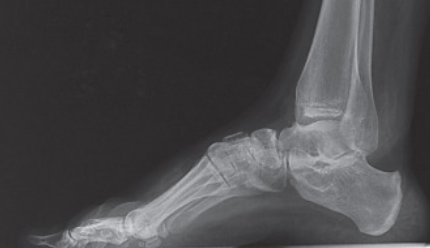

Maria de Lluc, responsable de Clínica Grimalt Llinàs, explica que es una deformidad del primer radio, una plantarflexión de la falange proximal que provoca dolores intensos a la hora de realizar una actividad física o al caminar.

Además, la patología Hallux Flexus, a parte de ser una deformidad, provoca un desequilibrio en el balance muscular. Dependiendo de la gravedad, suelen aparecer Hiperqueratosis o dolores intensos mientras el pie está en reposo.